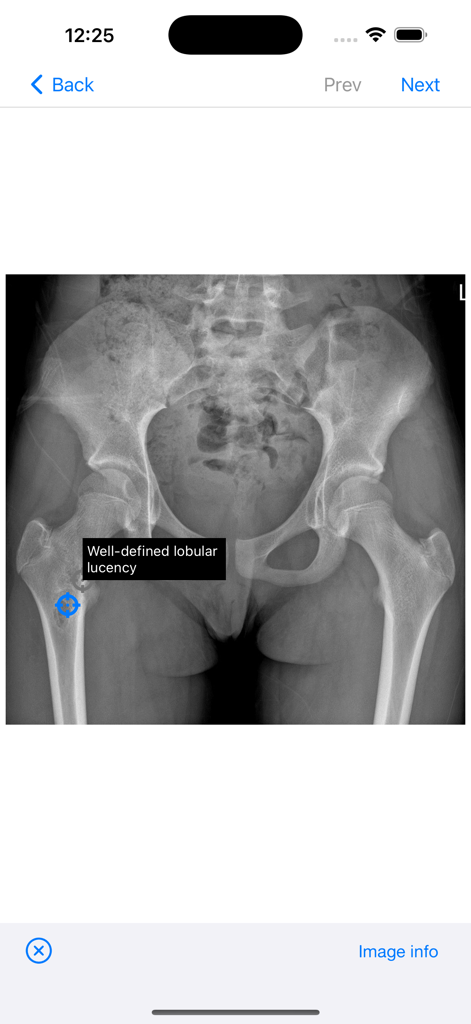

BoSTT - Pelvic xray with a well defined lobular lucency highlighted in the femur on the BoSTT app

Pelvic xray with a well defined lobular lucency highlighted in the femur on the BoSTT app